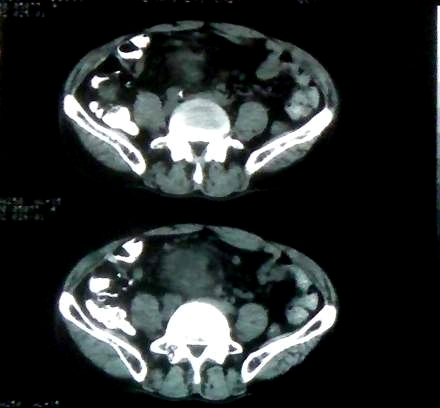

男 60岁,下腹部肿块半年余

前列腺肥大,密度不均。伴盆腔实性肿块。考虑前列腺癌伴盆腔转移。建议增强扫描。

考虑来源于肠道的肿瘤,乙状结肠?询问排便情况

盆腔恶性占位,间质瘤可能性大

乙状结肠间质瘤

盆腔恶性占位,间质瘤可能性大。

考虑盆腔内间质瘤可能性大。

病理结果:肠系膜肉瘤

病灶形态不规则,偏心性裂隙样坏死,支持恶性病变。来源不好定。感谢反馈结果--肠系膜肉瘤。